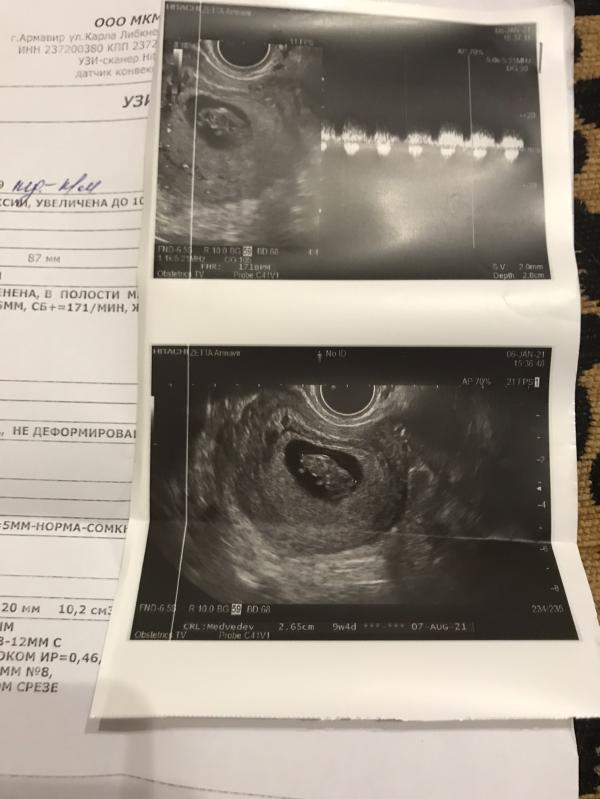

Девчонки всем привет планирующем и уже беременяшкам Сегодня была на узи 9 недель перед постановкой на учёт. Что скажите ?

А почему угроза выкидыша? Что сказали на узи?

Из-за тонуса матки а тонус из-за стоячей и тяжёлой работы

Все нормально,только тонус есть